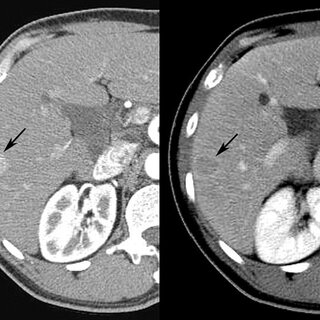

يمكن لأجهزة التصوير المقطعي المحوسب إجراء العديد من تقنيات التصوير المتخصصة ، مثل التصوير المعزز بالتباين (#Contrast_Enhanced Imaging). يتم إعطاء عوامل التباين (Contrast Agents) لتسليط الضوء على أنسجة أو أوعية دموية معينة ، مما يساعد في الكشف عن بعض الحالات وتوصيفها. 🌡️💉